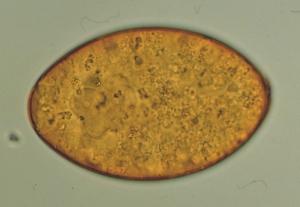

Photo Laboratoires Mérial

Les œufs (140 x 80 µm) sont ovoïdes, operculés, de couleur jaunâtre avec un contenu granuleux et homogène. Leur élimination dans le milieu extérieur se fait de façon irrégulière en fonction du rythme des vidanges biliaires (de 3 à 4.000 oeufs peuvent être éliminés quotidiennement par un adulte). Le plus souvent l'œuf subit un premier développement embryonnaire avant d'être éliminé. Les œufs de Fasciola hepatica résistent peu de temps à la dessication ou au gel, mais peuvent survivre jusqu'à 1 ou 2 ans dans un environnement froid et humide.